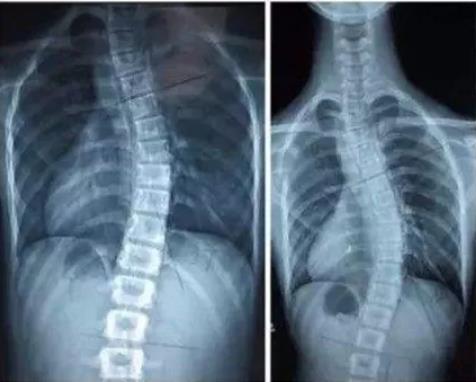

今天,在丽水市第二人民医院脊柱侧弯康复门诊内,12岁女孩小叶被诊断患有中度脊柱侧弯,胸段侧弯30°。据康复医学科副主任吴小山介绍,现在小叶需要积极配合治疗,若是脊柱侧弯幅度不断增大,那以后就需要手术治疗了。

一想到女儿的脊柱要被钉上一颗颗矫正钢钉,再旋转矫正,小叶的妈妈不禁后怕。

“平常孩子走路、看书时,我们都没发现有什么不对的地方。看到二院推送的微信后,我们开始留意孩子,在她洗澡时,才发现她弯腰时后背两边不对称,今天一早就赶紧带来看了。”